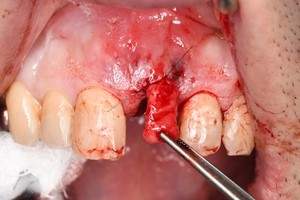

症例写真-2

- Befor

- 途中経過

- After

| 年齢 | 50代・男性 |

|---|---|

| 主訴 | 右下歯が疼く |

| 治療内容 | ・右下6番インプラント ※1:FGG(遊離歯肉移植術)とは、足りない歯ぐきを上顎から上皮を切り取り移植する外科手術 |

| 治療費 | 合計:902,000円(税込) ■内訳 |

| 治療期間 | 9ヵ月 |

| 治療方針 | 右下の当該歯は歯根破折により保存不可能と診断しました。歯周疾患も伴っていたため抜歯後に骨吸収※1が大きく起こることが予測できました。チタンメッシュ併用骨再生誘導法(GBR※2)を選択しインプラント埋入と同時に行い自然な歯槽骨のラインを再現しました。またGBRを行う際にインプラント辺縁の付着歯肉の減少が起こる為、遊離歯肉移植術(FGG※3)を行い清掃性を考慮した形態に仕上げました。 ■治療方針の解説 治療した右下の歯をレントゲンで撮影したところ根本の部分に黒く写る箇所があり「根尖性慢性周囲炎※1」と診断。また歯周病も進行していました。 ※1 骨吸収・・・歯槽骨という歯を支える骨がなくなっていくこと |

| 担当者所見 | 主訴の右下だけでなく歯茎の腫れ、発赤があり不良補綴や不良充填など他にも治療箇所が多数ありました。プラークコントロールが不良であった為まずはブラッシング指導を行いセルフケアの重要性を理解していただくところからスタートしました。 右下6番の歯はインプラント治療を行なった結果審美的にも機能的にも患者様の満足を得ることができました。骨造成と歯肉移植も行なった為インプラントを支える十分な歯周組織の獲得ができたと思っております。 |